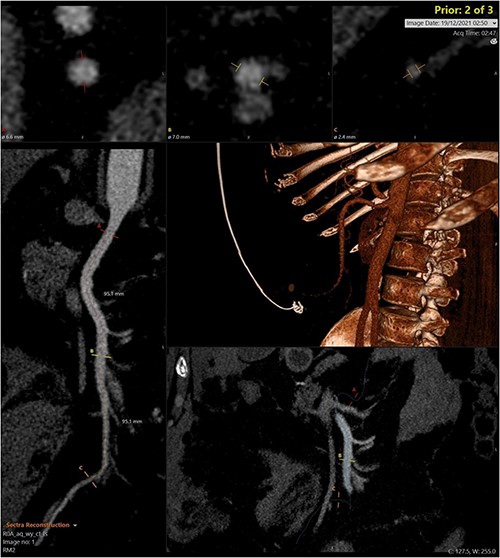

A CT abdomen-pelvis (CT-AP) revealed an acute haematoma inferolateral to the third part of the duodenum and another at the root of the mesentery. High density fluid related to the mesenteric bleed was also seen extending from the right para-colic gutter into the pelvis and in the peri-hepatic region. The patient was admitted under general surgery, stabilized with intra-venous fluid resuscitation, co-amoxiclav and metronidazole and cross matched for four units of blood. A CT-angiogram demonstrated acute haemorrhage throughout the abdomen with a 104 x 62 mm haematoma arising centrally at the level of L2 within the mesenteric fat (Fig. 1). The haematoma did not appear to originate from any specific mesenteric vessels but was related to some mid and distal jejunal loops. The angiogram also showed discontinuity when tracing the proximal and mid jejunal loops inferiorly, extensive haemorrhagic peritoneal fluid around the liver extending inferiorly (Fig. 2) and a small amount of peri-splenic haemorrhagic fluid. Curved reformatting of the angiogram revealed no abnormalities within the superior mesenteric artery (Fig. 3).

CT angiogram showing a large acute mesenteric haematoma. Figure 1 is taken from an axial section of the patient’s initial CT angiogram of the abdomen and pelvis. The arrow shown highlights an area of high-density fluid representing a 104 x 62 mm acute mesenteric haematoma.